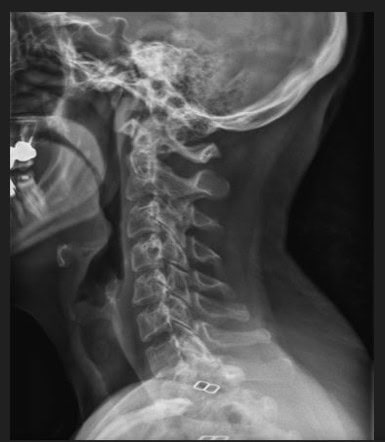

Pre Scan